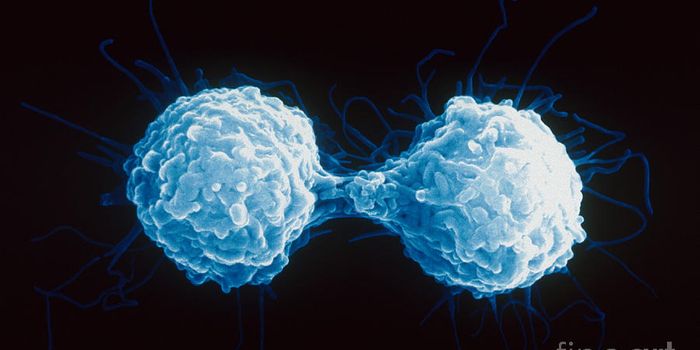

DEC 10, 2015ImmunologySuperior technology brings us novel images of cancer cells and lymphocytes this week, and now scientists can learn more ...